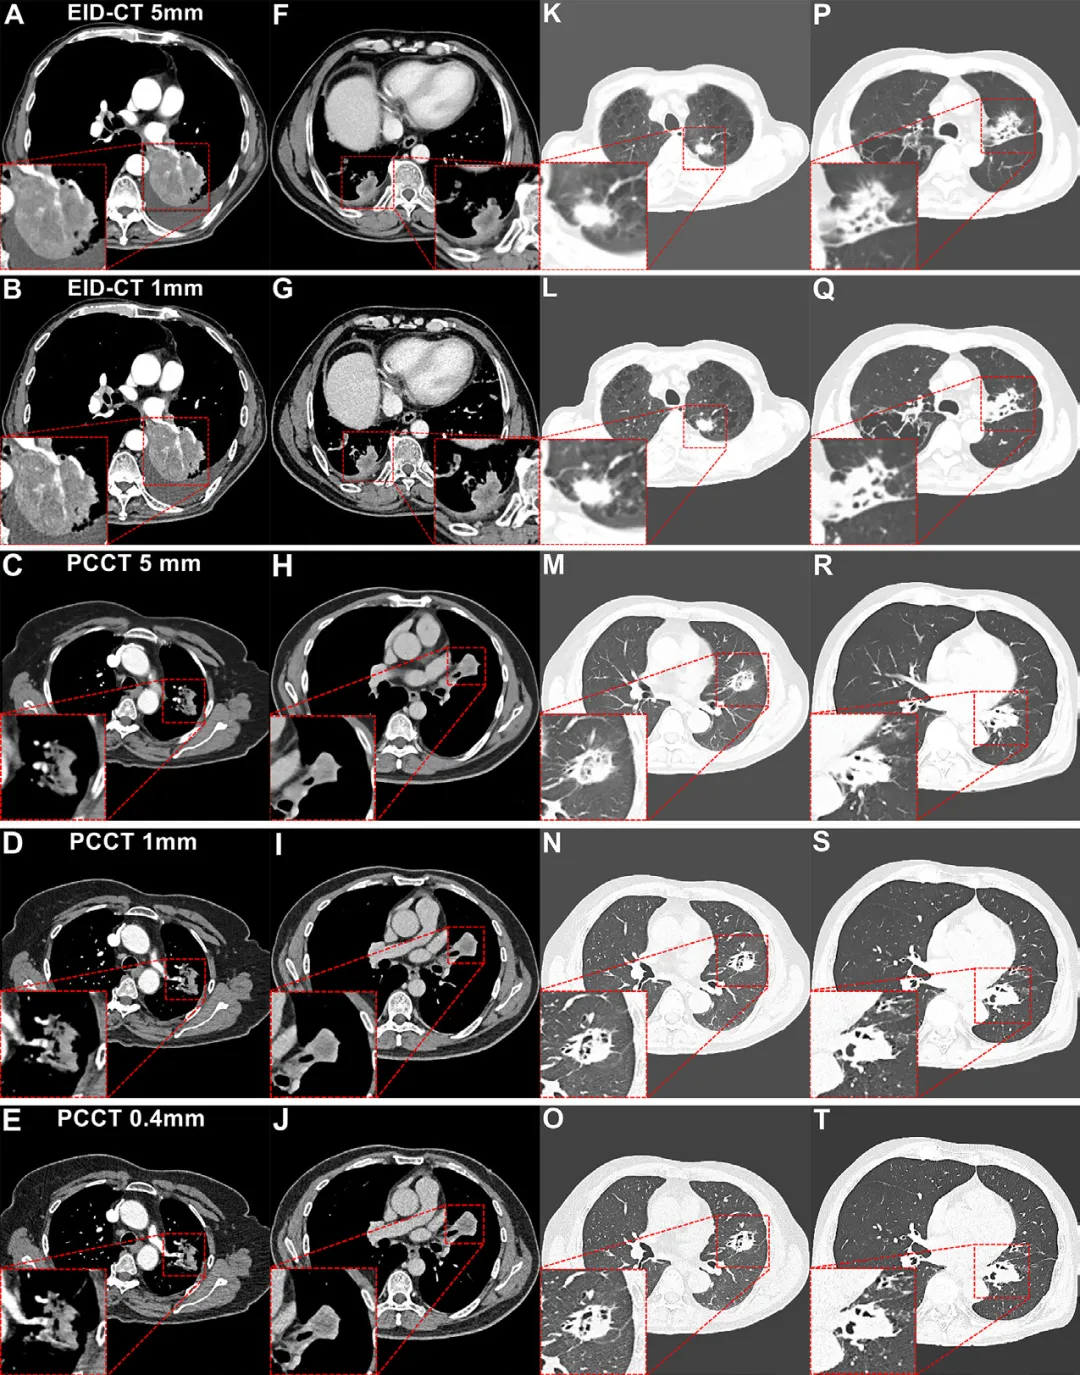

扫描与重建:PCCT使用双源量子CT(NAEOTOM Alpha),采用120 kV、UHR模式(准直120×0.2 mm),重建层厚包括5 mm、1 mm、0.4 mm。EID-CT采用相同造影剂浓度(350 mg I/mL),重建层厚为5 mm与1 mm。

图像质量提升:1️⃣PCCT在5 mm与1 mm层厚下噪声更低、SNR与CNR更高;0.4 mm层厚在噪声方面与EID-CT 1 mm相当,但空间分辨率显著提升。2️⃣主观评分显示PCCT 0.4 mm在“增强病灶内结构”显示上优于EID-CT,尤其在正常体重与小肿瘤(≤3 cm)患者中整体图像质量最佳。

恶性特征检测与诊断信心:1️⃣PCCT 0.4 mm检出更多增强相关恶性特征(如血管汇聚、支气管截断),总数显著高于EID-CT(291–340 vs 194–255)。2️⃣诊断信心评分PCCT 0.4 mm显著高于EID-CT 1 mm,尤其在毛刺征、分叶征等特征上。

亚组表现差异:1️⃣BMI越低,PCCT图像质量优势越明显;超重患者中PCCT仍改善主观评分,但CNR受噪声影响有所下降。2️⃣小肿瘤(≤3 cm)在0.4 mm层厚下结构显示更清晰;大肿瘤(>3 cm)则在1 mm层厚下边界对比更佳,提示应根据肿瘤大小个性化选择重建层厚。

图4:EID-CT与PCCT的肺癌增强CT图像示例,展示血管汇聚征、坏死区边界、毛刺征、支气管狭窄征等特征。